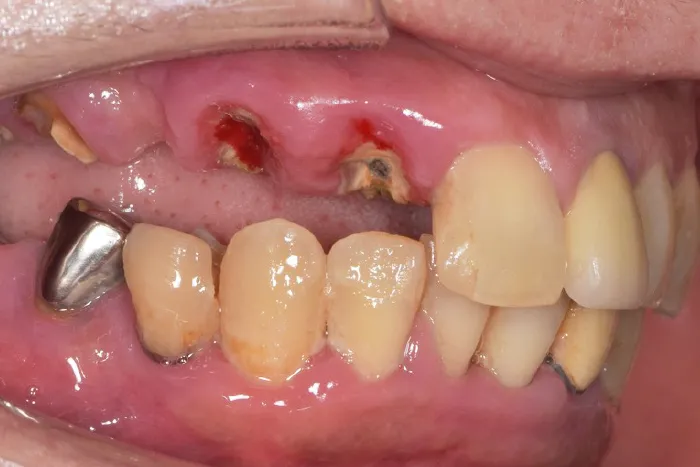

重度歯周病

さらに根尖方向に進行します。

骨を溶かすことによりポケットの深さ6mm以上。

嫌気性菌は、歯周ポケットの中で黒い歯石を作りバイオフィルムの形成を行います。

歯の根っこの長さは平均10mm です。

骨の吸収により、歯が揺れはじめます。

◆症状

歯茎の腫れ・出血・歯の浮いたような感覚・歯茎の低下・歯の動揺。

レントゲン上で、重度の骨の吸収、歯肉縁下に歯石を確認できます。